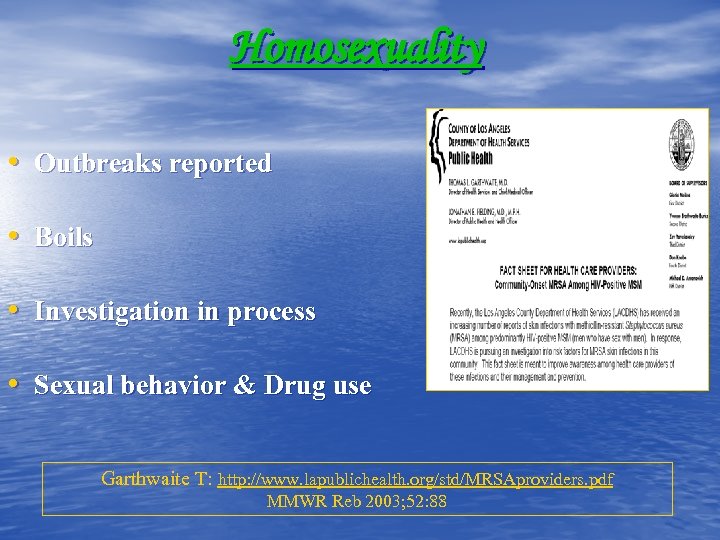

Homosexuality • Outbreaks reported • Boils • Investigation in process • Sexual behavior & Drug use Garthwaite T: http: //www. lapublichealth. org/std/MRSAproviders. pdf MMWR Reb 2003; 52: 88

Homosexuality • Outbreaks reported • Boils • Investigation in process • Sexual behavior & Drug use Garthwaite T: http: //www. lapublichealth. org/std/MRSAproviders. pdf MMWR Reb 2003; 52: 88